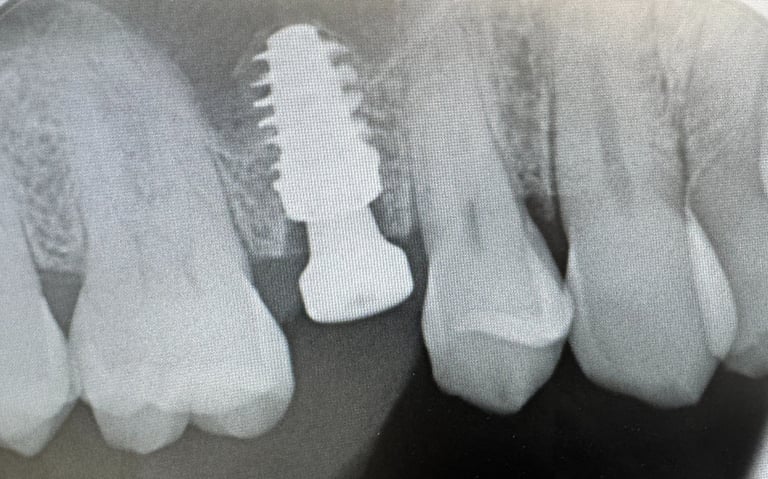

Hammasimplantti on titaaninen tai keraaminen 'ruuvi' joka asetetaan luuhun. Tämän varaan voidaan valmistaa yksilöllinen hammas.

Mielestäni kyllä. Ja siksi käytän vain Straumann -implantteja. Niiden avulla saadaan paras mahdollinen rakenne ennustettavalla luutumisella. Myös tärkeää on että tulevaisuudessa on osia tarvittaessa saatavana. Maailmassa on noin 600 eri implanttimerkkiä käytössä ja olen valinnut Straumann implantit juuri näistä syistä. Straumann implantit on olleet kymmeniä vuosia markkinoilla ja tutkimus niiden osalta on perusteellista.